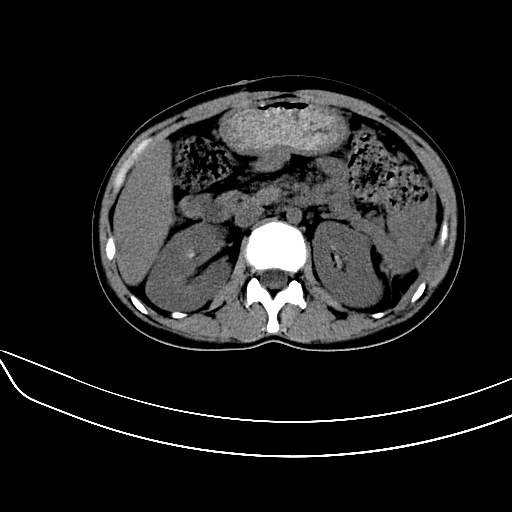

女,22岁,临床以糖尿病等病史入院,两年前有妊娠合并胰腺炎史,现有多饮、多尿、咳嗽、咳痰、左腰痛、发热等。因多种原因没做增强。

图象发的太少,第二幅图肝左内叶低密度影中似有更低密度影,建议强化.

考虑:1、不均匀性脂肪肝(肝大+不均质密度);

肝、脾增大,内见多发低密度影,少量腹水,左侧肾周筋膜增厚,结合病人糖尿病史,有左腰痛、发热,考虑:糖尿病激发肝脾病变(梗塞?),左侧肾周感染,建议进一步检查。

真可惜,这么年轻就重病缠身,患者肝内,脾,肾,左下肺,左腰大肌均见病变,结合病史考虑感染可能性大。